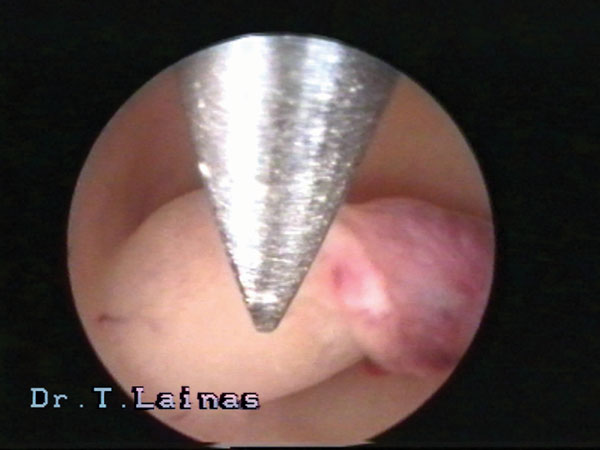

Η εφαρμογή της υστεροσκοπικής χειρουργικής αποτελεί τη σύγχρονη αντιμετώπιση των καλοηθών παθολογικών καταστάσεων της κοιλότητας της μήτρας και ιδιαίτερα αυτών που σχετίζονται με την υπογονιμότητα. Παράδειγμα υστεροσκοπικών επεμβάσεων αποτελούν η λύση ενδομητρικών και ενδοτραχηλικών συμφύσεων, η αφαίρεση πολυπόδων και υποβλεννογονίων ινομυωμάτων μήτρας και η διατομή διαφράγματος μήτρας.

Αρκετοί υποστηρίζουν ότι υπάρχει αύξηση των ποσοστών επιτυχίας κυήσεως μετά την υστεροσκοπική χειρουργική διόρθωση των καλοήθων παθολογικών καταστάσεων της μητριαίας κοιλότητας